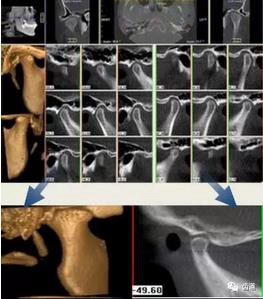

四)口腔腫瘤和顳下頜關(guān)節(jié)疾病

CBCT在口腔腫瘤和顳下頜關(guān)節(jié)疾病的診斷與治療及口腔整形美容易達成理解和配合,提高患者對牙病治療的接受程度和滿意度,為口腔臨床教學(xué)和科研提供必要的信息資料,與根尖片、全景曲面斷層對比更為優(yōu)越突出。

1、頜骨腫瘤

下頜骨占位病變影像

2、整形美容

整形美容假體測量應(yīng)用影像

3、顳下頜關(guān)節(jié)

顳下頜關(guān)節(jié)CBCT影像